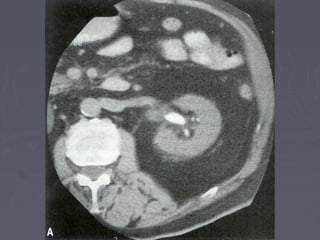

Mis imágenes2005-04 (abr)litiais.jpg